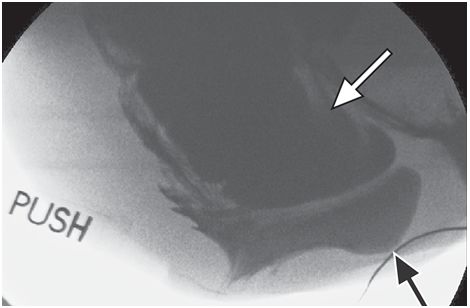

小肠膨出和乙状结肠膨出指小肠或冗长的乙状结肠下降到盆腔深部,压迫直肠的前或上壁,严重时能引起排便梗阻(图4)。小肠和乙状结肠膨出能下降到直肠子宫陷窝,甚至脱垂出肛门(图5)或者阴道口。这些情况常见于子宫切除术后或多次分挽,导致盆内筋膜连续性中断的患者。外科手术修复包括腹膜内容物的悬挂,防止疝的形成。

图4 小肠膨出(白箭)。力排期含钡的小肠下降到直肠阴道间隙,压迫直肠(黑箭),同时也有直肠膨出

图5 盆底腹膜疝。随着排便力度加大,小肠、大肠经过肛门脱垂(A-C)。直肠位于后方(黑箭),乙状结肠和小肠位于前方(白箭)